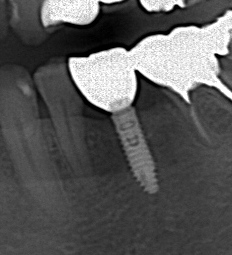

抜歯後インプラントを埋入しましたが骨が足りずネジが

見えています。

人工骨を填入しメンブレンを敷いたところです。

レントゲンでは外側に人工骨を足したため

像としては現れにくいです。